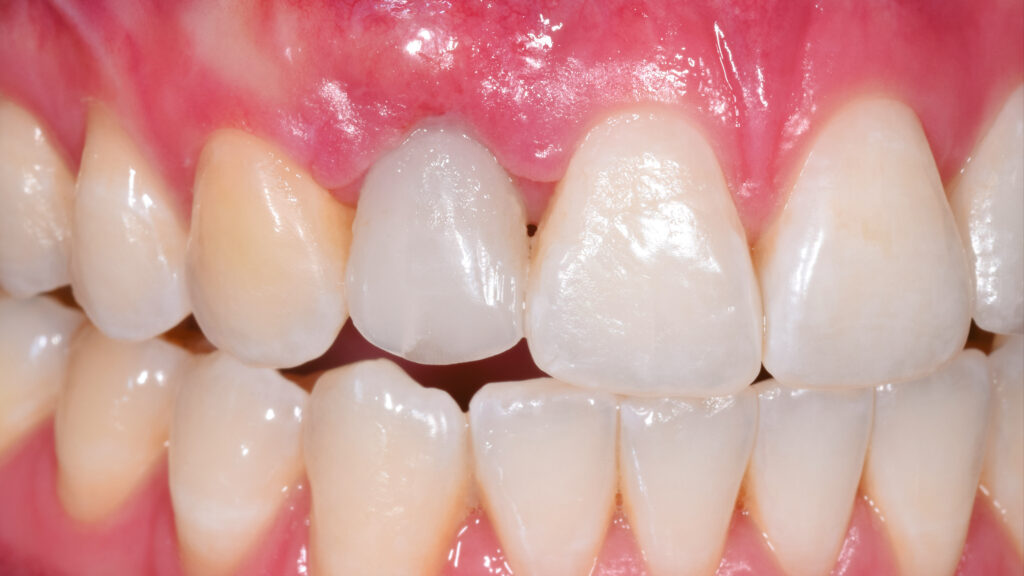

Ein Blick auf die Ausgangssituation (Abb. 1) verdeutlicht die Problematik bei diesem jungen Patienten. Der Milchzahn in regio 12 ist stark verfärbt. Zusätzlich beeinträchtigt der verkleinerte Zahn 22 (Mikrodontie) das ästhetische Bild. Auch der Gingivaverlauf erscheint unharmonisch. Abbildung 2 zeigt die Situation nach kieferorthopädischer Erstbehandlung. Während dieser Behandlungsphase konnte im Frontzahnbereich Platz für das Implantat (TiUltra, Nobel Biocare, Zürich, Schweiz) regio 12 und für das Keramikveneer an Zahn 22 geschaffen werden. Dies bildet die Grundlage für ein natürliches und harmonisches Erscheinungsbild.

Paradigmenwechsel:

In der Zahnarztpraxis wird der Milchzahn schonend extrahiert und das TempShell-Provisorium mit seinen zwei Flügeln im Mund des Patienten einprobiert (Abb. 38). Nach der Sofortimplantation des Implantates regio 12 erfolgt eine Konturverbesserung, die im Rahmen der Freilegung korrigierend zur Weichgewebsverdickung vorgenommen wird. Dadurch soll ein graues Durchschimmern des Titans verhindert werden (Abb. 39). Einige Wochen später kommt der Patient zur Kontrolle in die Praxis. Die Heilung der Gingiva ist gut. Das Gingivaniveau konnte weiter nach apikal gelegt werden, um einen harmonischeren Gingivaverlauf zu erzielen (Abb. 40 und 41).